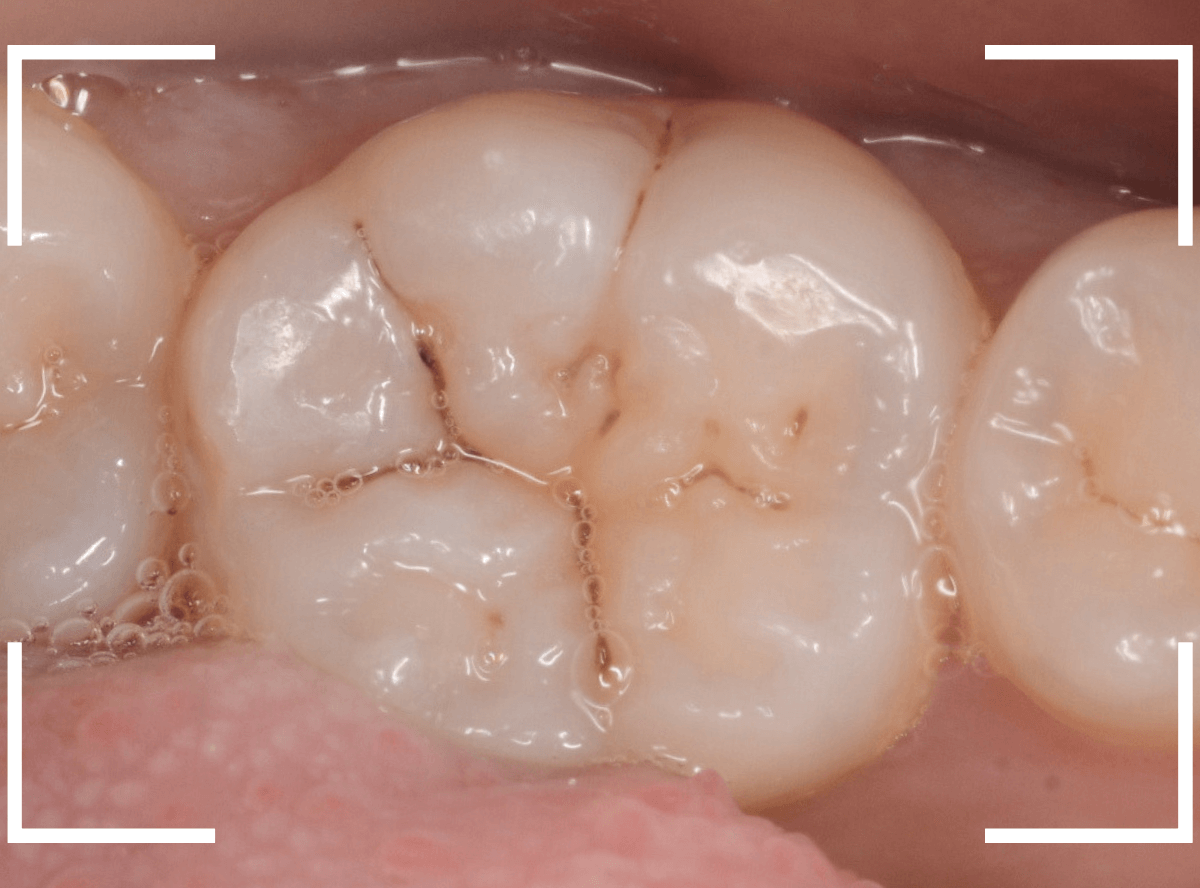

特に症状はありませんが、歯の咬頭(噛み合わせの山の部分)に小さな穴が空いていて、その周りがもやっと黒く見え、虫歯が怪しいです。

レントゲン写真で確認しますが、ここでは特に問題はなさそうに見えます。

患者さんに状況を説明し、慎重に削って調べる事になりました。

少しずつ穴の部分を削ってみると、ズブッと落とし穴にはまるような柔らかい虫歯の層(=軟化象牙質)に当たりました。

慎重に虫歯を除去したところです。

歯の溝のレジンが詰めてあった部分まで虫歯は進行していました。

とはいえ、それほど深く虫歯は進行していませんでしたので、虫歯除去後、レジンを充填して治療は終われました。

このように定期的にメンテナンスに来ていただくと虫歯が本格的に進行する前に対処する事ができます。